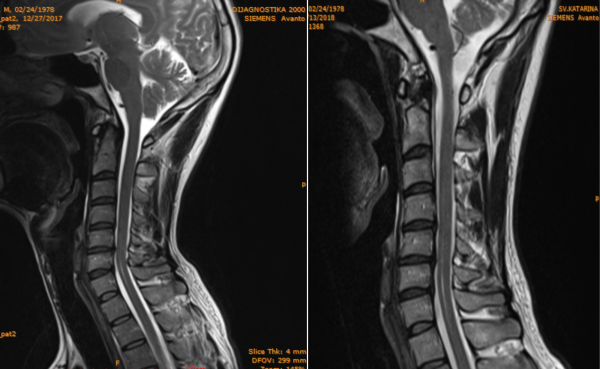

MR snimka rađena u razmaku od 6 mj. pokazuje stanje kralježnice prije i stanje kralježnice uz redovito vježbanje DNS tehnikom.